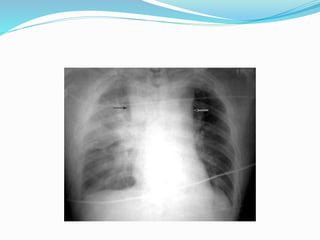

Chest x ray:

• Nonspecific

• Wide mediastinum or loss of normal aortic knob

contour is common (up to 76 %)

• Demonstrates air in pleural space